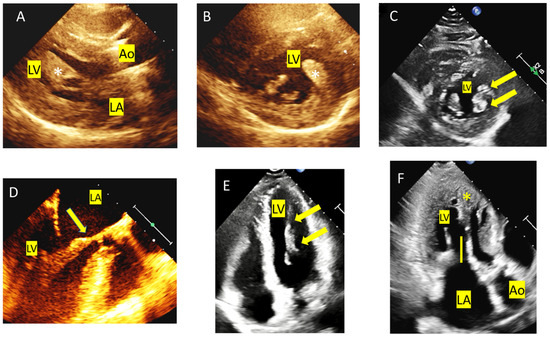

4. Tip and Tricks Concerning LVOT Obstruction Doppler Measurement

5. Mitral Valve Anomalies

6. Left Ventricular Anomalies